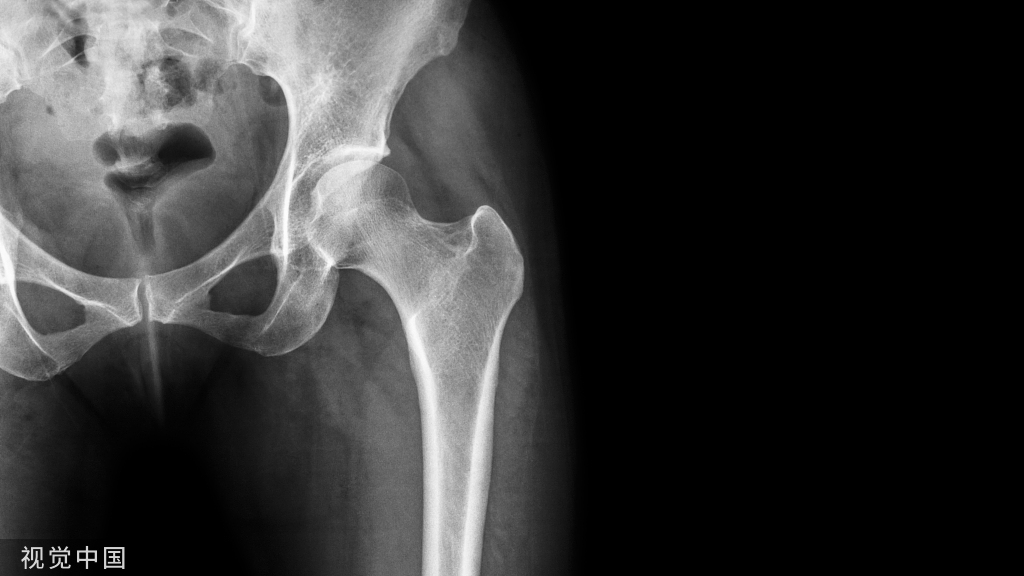

L1爆裂骨折

侧前方减压术后CT表现